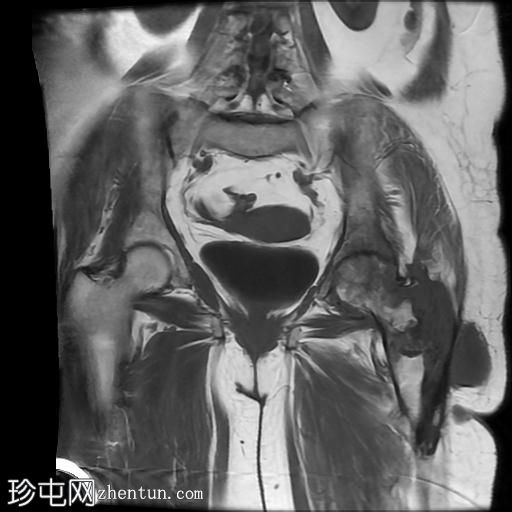

冠状位

T1加权像

4.jpg

冠状位T2加权像

5.jpg

脂肪抑制像

6.jpeg

左髋关节存在严重的关节病变,表现为关节间隙显著变窄、软骨丢失、软骨下骨髓水肿以及囊性改变。

此外,左股骨颈基底部、股骨粗隆间区及股骨大转子区域可见骨髓信号异常及皮质破坏。伴有滑膜增厚及较大的冷脓肿腔,提示左股骨颈及股骨粗隆间区骨髓炎。

另一处较大的冷脓肿从股骨受损部位开始向上延伸至左侧臀肌。

在左侧股骨外侧皮下可见低信号窦道。